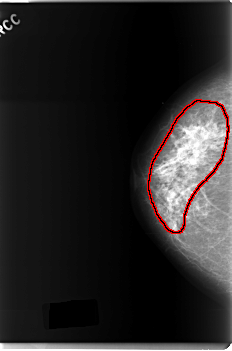

C_0179_1.RIGHT_CC

RIGHT_CC LINES 5960 PIXELS_PER_LINE 3928 BITS_PER_PIXEL 12 RESOLUTION 50 OVERLAY

FILE: C_0179_1.RIGHT_CC.OVERLAY

TOTAL_ABNORMALITIES 1

ABNORMALITY 1

LESION_TYPE CALCIFICATION TYPE PLEOMORPHIC DISTRIBUTION REGIONAL

LESION_TYPE MASS SHAPE IRREGULAR MARGINS ILL_DEFINED

ASSESSMENT 5

SUBTLETY 5

PATHOLOGY MALIGNANT

TOTAL_OUTLINES 1

BOUNDARY